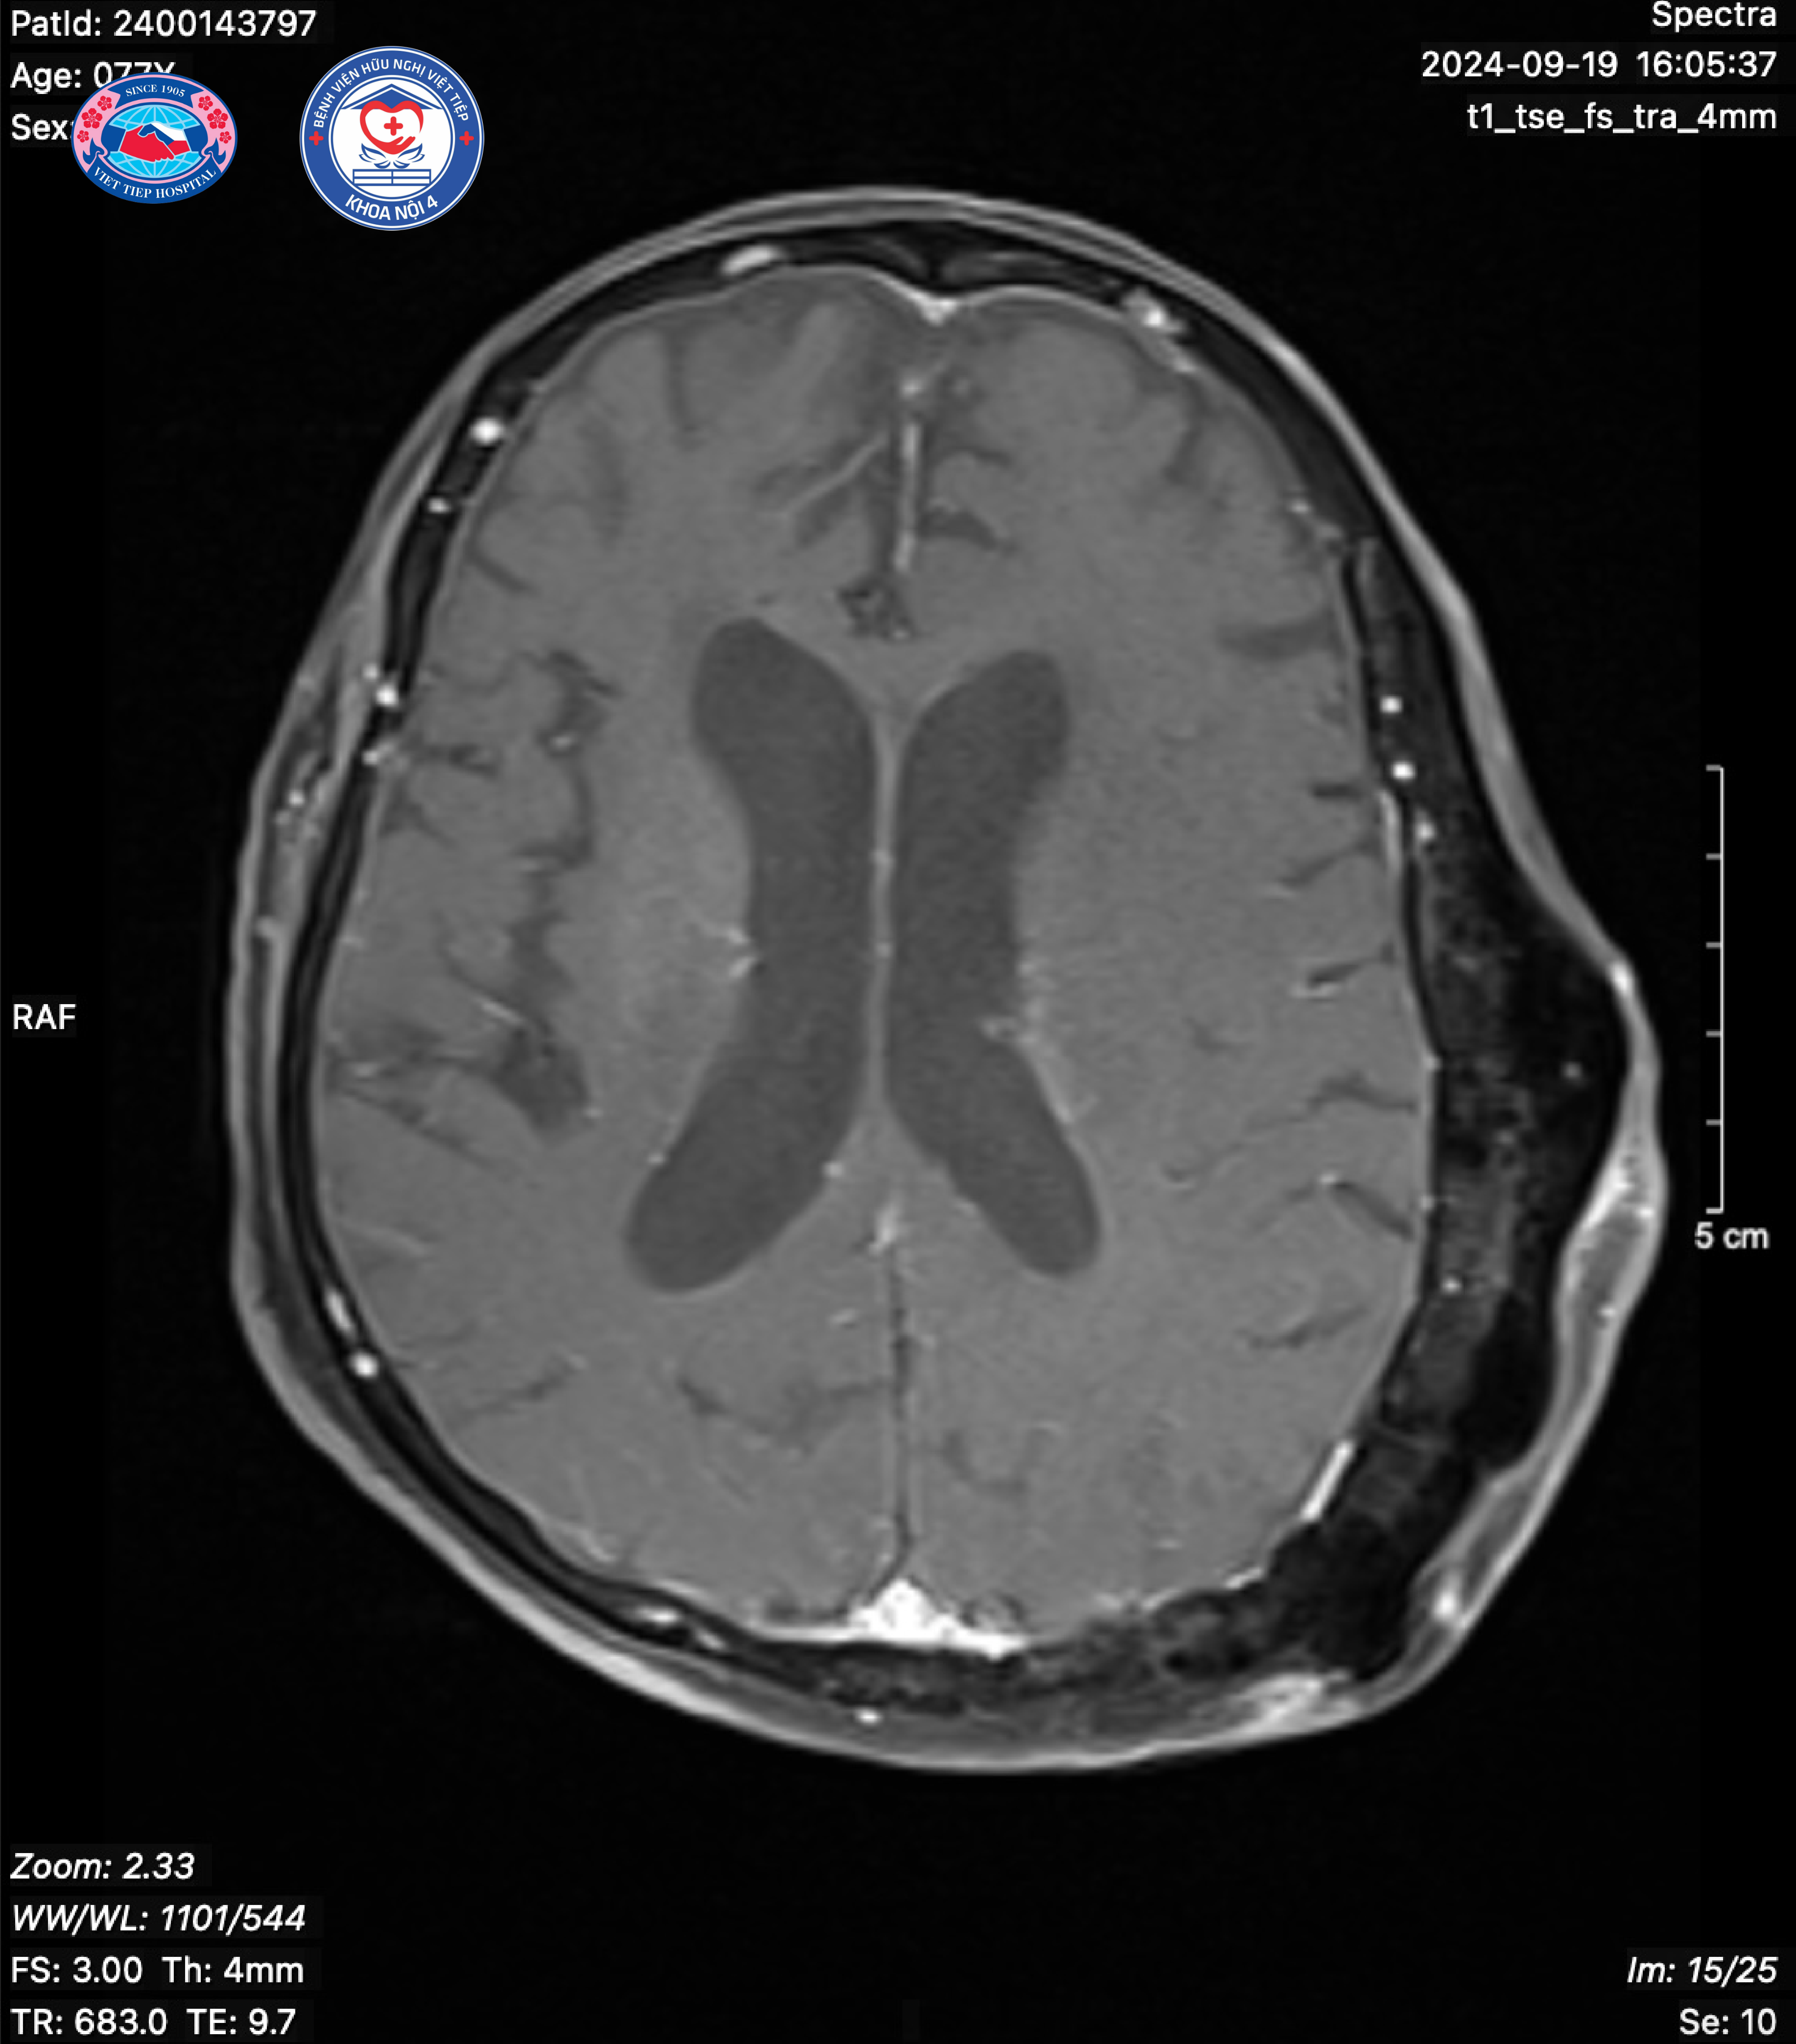

(Hình ảnh Loạn sản xơ xương sọ não ở người bệnh 77 tuổi)

Thể đa ổ (30% trường hợp): Bệnh nặng hơn với tổn thương nhiều nơi và lan rộng, gây nhiều triệu chứng và biến chứng. Bệnh thường phát hiện sớm dưới 10 tuổi. Thường là một phía của cơ thể bị mắc bệnh. Tuy nhiên khoảng 1/4 số bệnh nhân tổn thương dạng đa xương bị tổn thương hơn một nửa khung xương, đặc biệt ở chi dưới. Tổn thương xương mặt sọ gặp ở 1/2 số bệnh nhân có tổn thương xương nhiều nơi. Khi tổn thương xương sọ mặt bệnh nhân có thể có các triệu chứng chèn ép thần kinh mạch máu như đau đầu, ù tai, bất thường thần kinh sọ não, thậm chí chảy máu sọ não tự phát. Loạn sản xương thái dương có thể giảm thính lực và bịt tắc hốc tai ngoài.

Chụp cộng hưởng từ hạt nhân: Đánh giá sự tiến triển của tổn thương, khả năng gãy xương bệnh lý, khả năng ác tính hóa của tổn thương xương, hay đánh giá tình trạng ép tủy khi cột sống bị tổn thương. MRI tiêm gadolinium cũng có thể đánh giá tình trạng tái phát sau mổ.